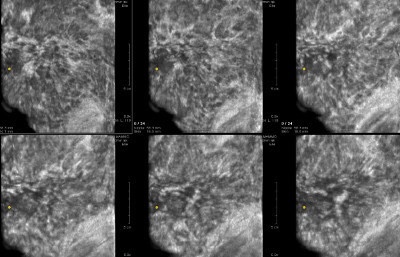

- The structural / architectural distortion:

- While difficult to detect mammographically:

- Is readily detectable on 2-mm thick coronal sections of automated breast ultrasound (Image)

- The 2-mm thick multi-slice series demonstrate the extensive architectural distortion, corresponding to the 3D histology: